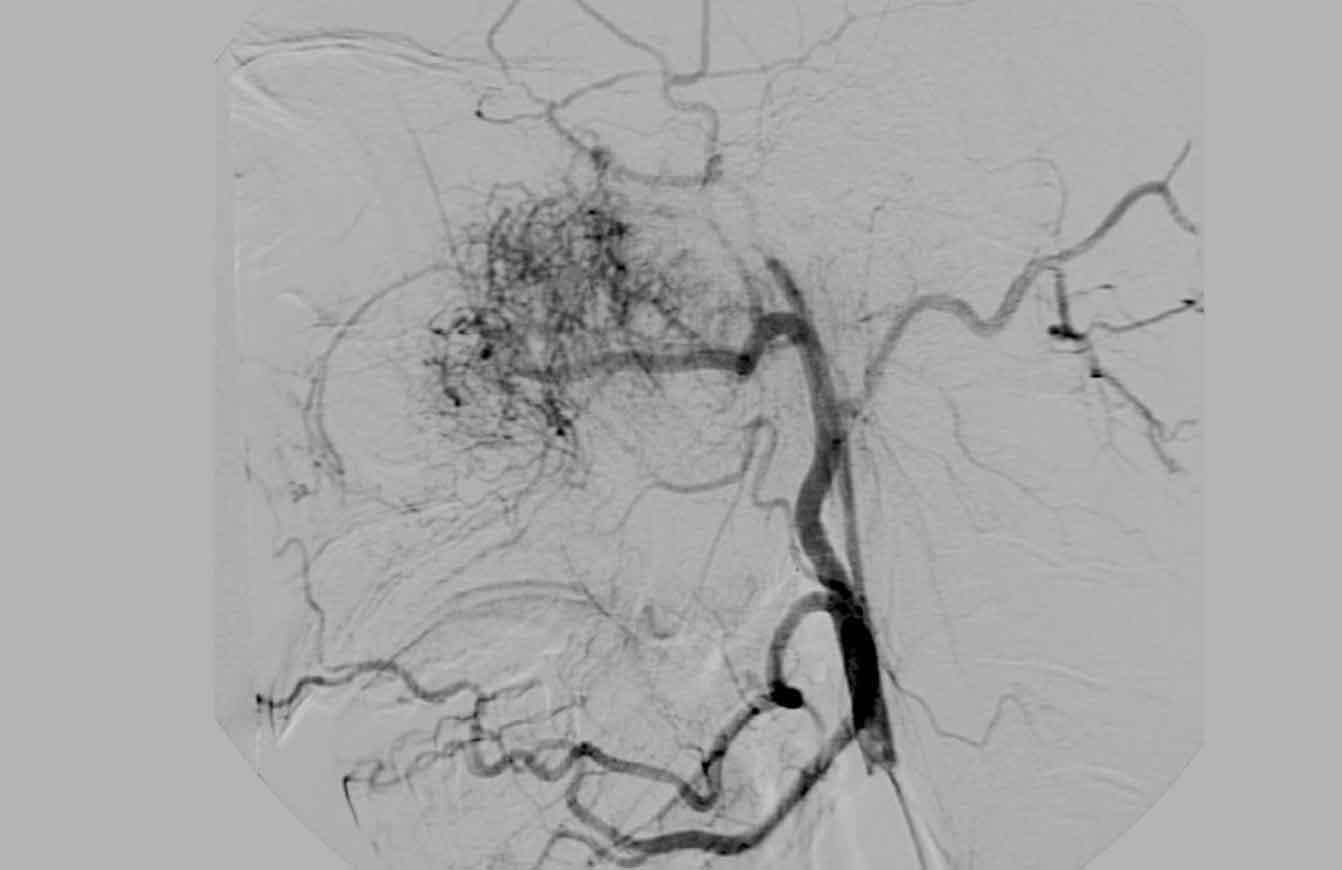

U xơ mạch máu vị thành niên (Juvenile angiofibroma)

Tiếp tục xem hình ảnh DSA…

Hình ảnh DSA cho thấy tình trạng tăng sinh mạch máu, điều này (kết hợp với vị trí đặc trưng) gợi ý mạnh mẽ cho chẩn đoán u xơ mạch máu vị thành niên.

Bệnh nhân này được điều trị tắc mạch (embolization) trước phẫu thuật.

Phẫu thuật cần được thực hiện triệt để nhất có thể để ngăn ngừa tái phát.

Tiếp tục xem hình ảnh MRI và DSA…

Và một lần nữa các dấu hiệu điển hình trên MRI và DSA.

Có ngấm thuốc mạnh và tăng sinh mạch máu rõ rệt.